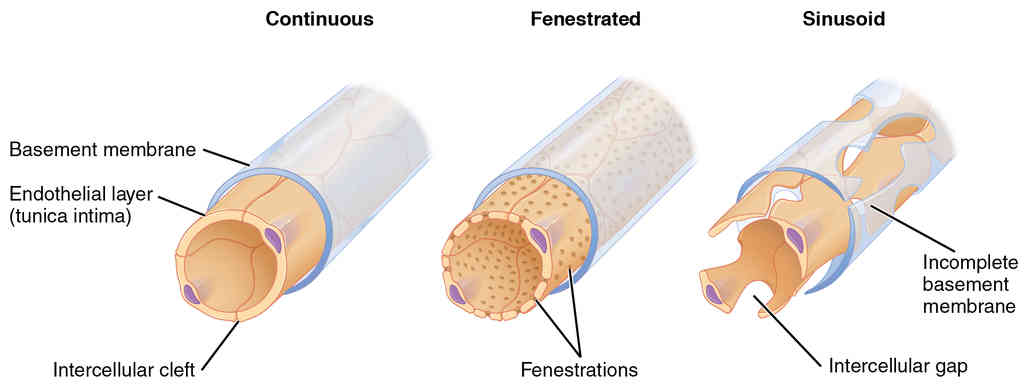

This page is under construction. For now, it is just a resource of the images found in the OpenStax Anatomy and Physiology Handbook. It wil slowly change into a revision tool. Each slide has a number. Use this to refer to the slide. When completed, it will have an unlabelled section, with labelled slides in parallel. On the unlabelled slides, write your answer and use the labelled slide to assess yourself. Keep track by also noting the number on each slide. Improvement at each attempt is important, more so than full marks on a first attempt.